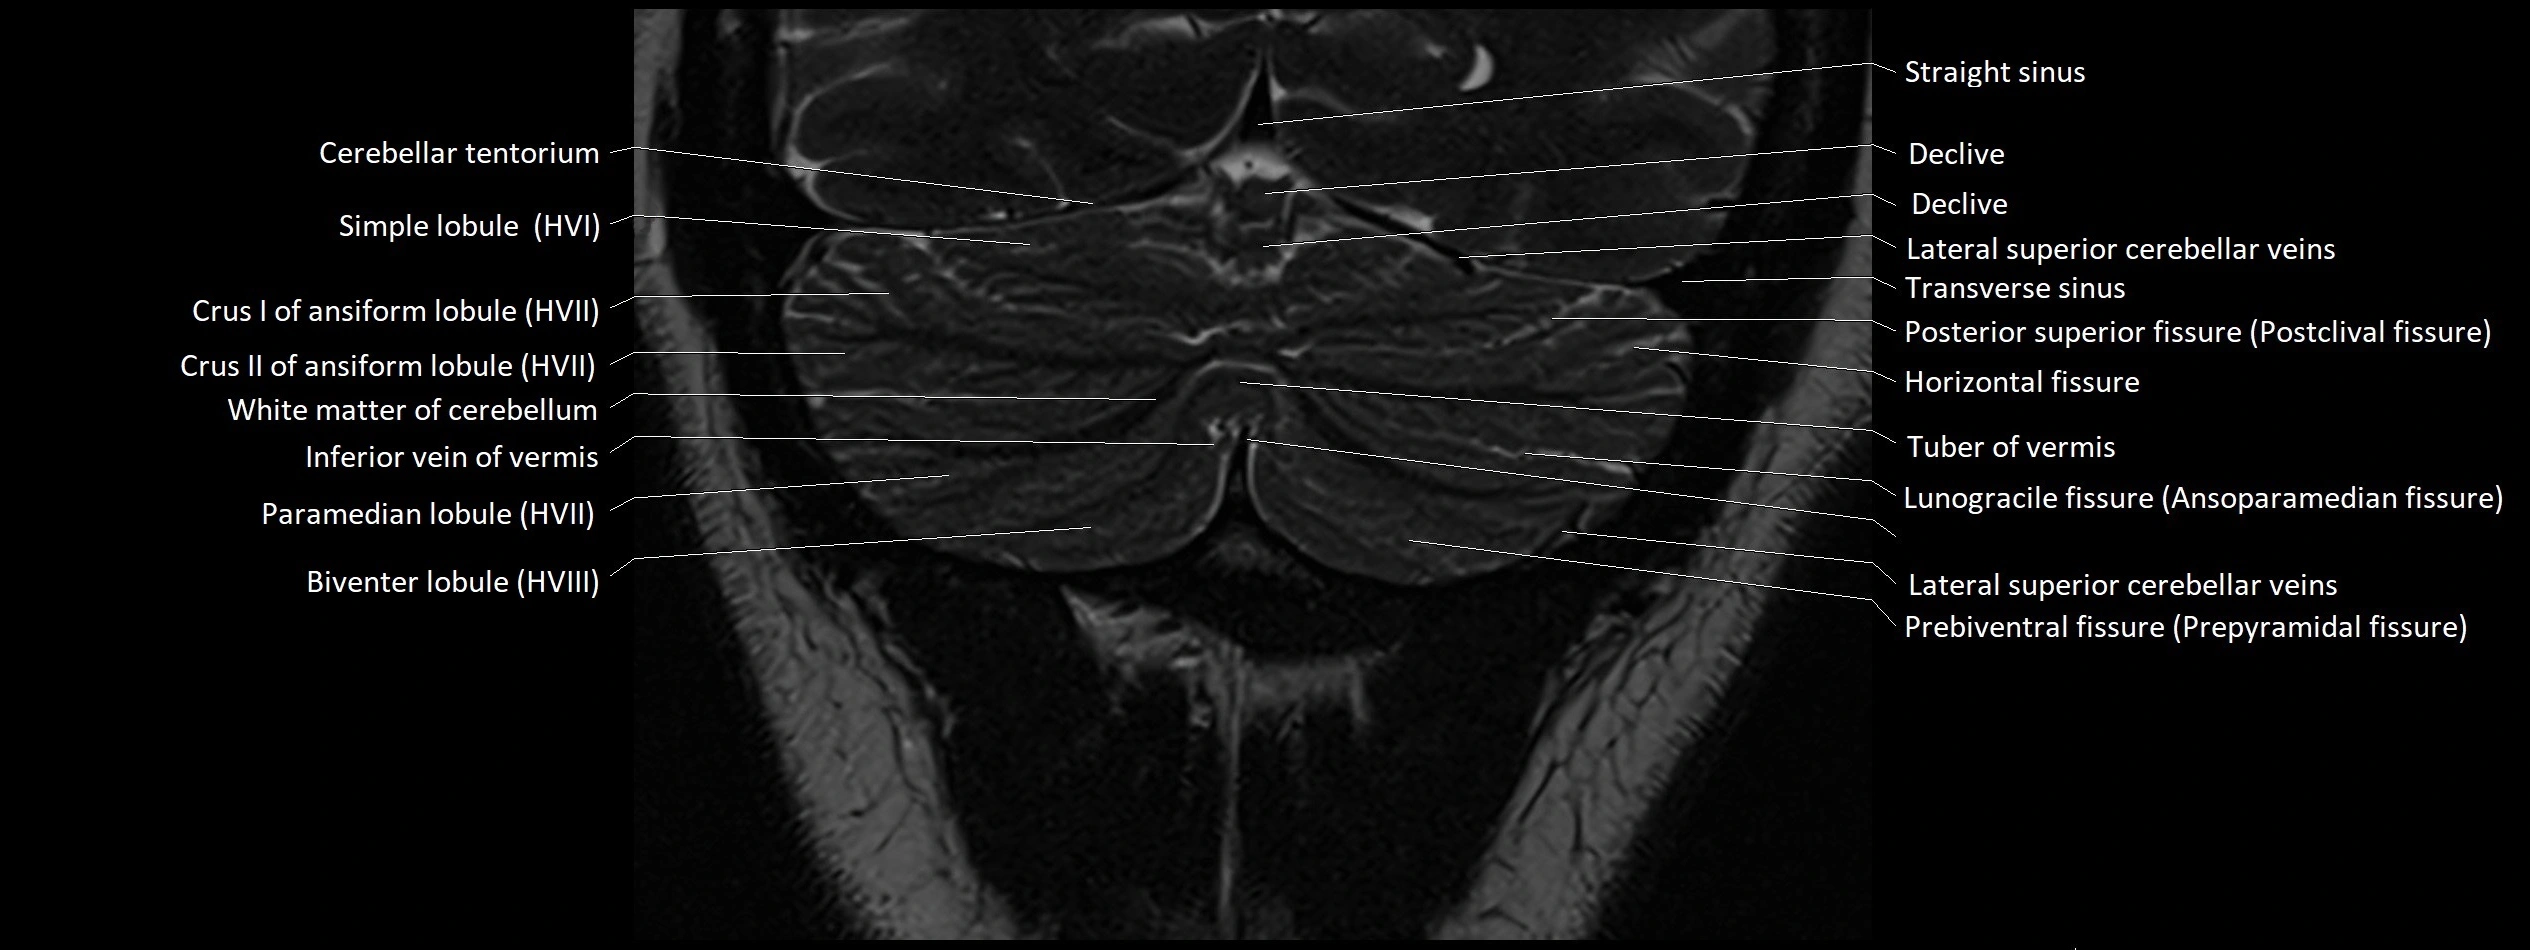

- Biventral lobule (HVIII) of cerebellum

- Cerebellar tentorium

- Crus I of ansiform lobule of cerebellum

- Crus II of ansiform lobule of cerebellum

- Declive

- Horizontal fissure (cerebellum)

- Inferior vein of vermis

- Paramedian lobule

- Paramedian lobule (HVII) of cerebellum

- Posterior superior fissure

- Simple lobule

- Simple lobule (HVI) of cerebellum

- Straight sinus

- Transverse sinus

- Tuber of vermis

- Tuber of vermis (VII)